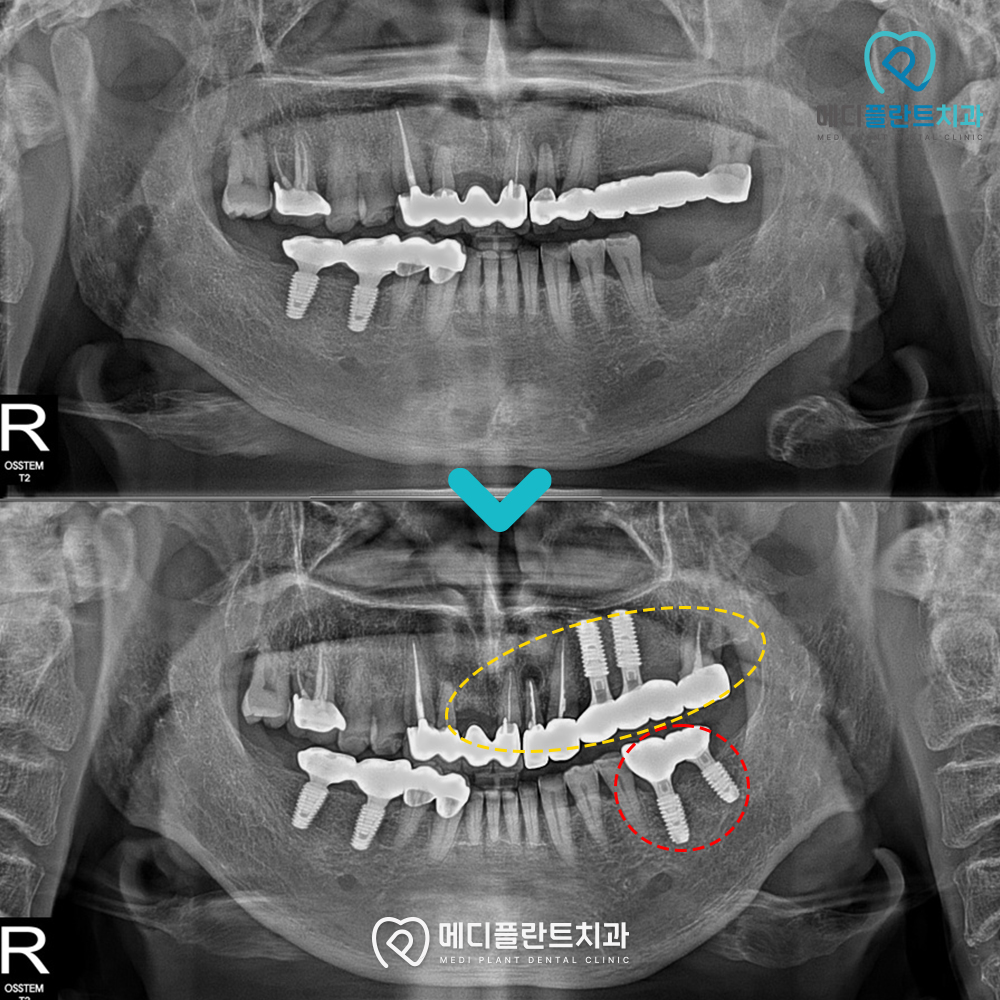

파노라마 촬영을 통해 상태를 확인해보니,

왼쪽 윗니와 아랫니 어금니 부위에

치아가 없는 것을 확인할 수 있었습니다.

.

특히 상악 어금니 부위에는

이전에 다른 치과에서 시술한

브릿지 보철물이 오래되어 교체가 필요했고,

아랫니까지 치아가 없어

한쪽으로만 음식을 씹게 되면서

턱관절 통증까지 동반되었습니다.

춘천수면치과 메디플란트치과에서는

환자분의 불편을 줄이고 저작 기능을 회복하기 위해

이전 브릿지 보철물은 임플란트로 교체하고

아랫니 빠진 자리에도 임플란트를 식립을 진행했습니다.

또한 앞니는 신경치료 후 보철물을 교체하여

자연스러운 미소를 되찾으실 수 있도록

심미적으로 개선했습니다.

최종 파노라마 사진을 보시면

임플란트가 안정적으로

자리 잡은 것을 확인할 수 있는데요.